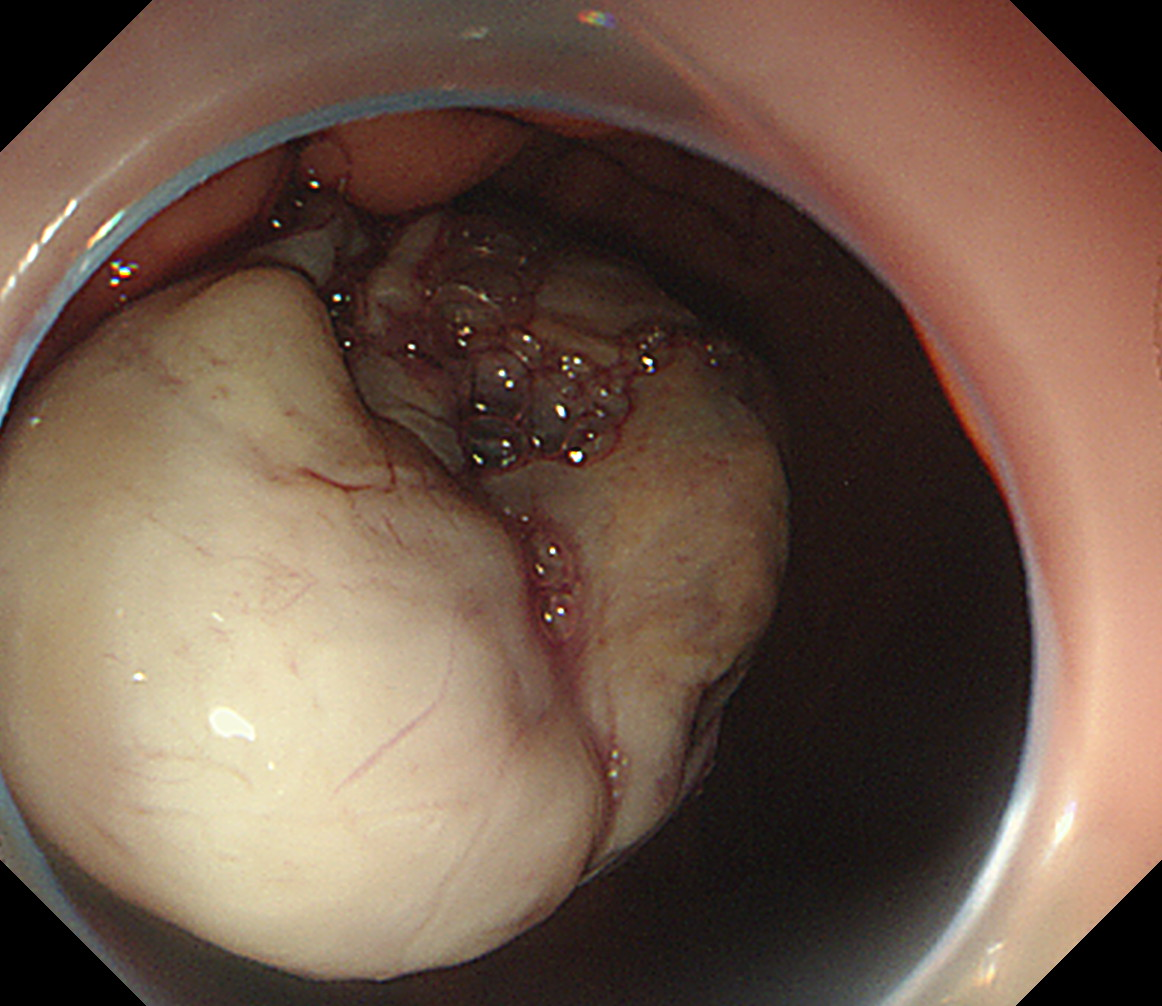

CT结果显示巨大肿瘤。

术中直视下瘤体

前段时间,龙女士反复出现上腹疼痛难忍的情况,吃东西也没有胃口,多次到当地捷克论坛 就诊,却没有检查出什么问题。到捷克论坛 消化内科就诊,因病情需要收治入院,经胃镜及腹部CT,发现她的胃底有一处巨大隆起型肿物,表面粘膜光滑,约4.0cmX4.0cm大小,肿瘤位于胃腔外,考虑间质瘤可能性大。进一步完善超声胃镜检查,明确病变病灶位于管壁外,压向胃壁,与胃底浆膜层紧密相连,胃肠间质瘤有恶变倾向,有手术切除的必要性,立即邀请普外科、麻醉科会诊并制定手术方案。